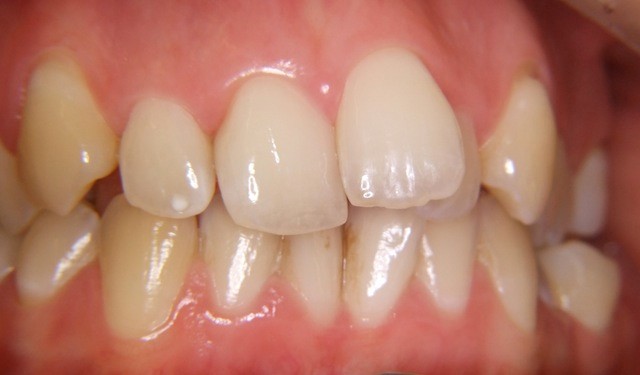

Beispiel einer Engstandsbehandlung bei einem Erwachsenen mit Invisalign

Vorher ----------------------------------- Nachher

Bilderserie Invisalignbehandlung Oberkiefer mit Stabilisierungsdraht am Schluss. Man beachte die Ansammlung von Belägen und Verfärbungen infolge Nischenbildung am Zahn der am meisten im Engstand steht.